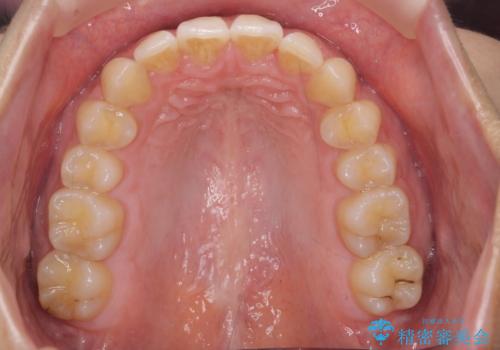

深いかみ合わせ 出っ歯の治療 インビザラインで

- 前歯の前突を主訴に来院。

かみ合わせが深く、また奥歯のかみ合わせも全体的に上が前にずれていました。

抜歯矯正も難しく、非抜歯矯正も歯の移動量が多くいずれにしても難易度が高い状態でした。

時間はかかりますが非抜歯で治療することにして、インビザライン矯正とワイヤー矯正を交互に行い仕上げました。

インビザライン矯正だけでなく、途中ワイヤー矯正もはさみました。前歯のかみ合わせが深く、本当に大変な治療でしたが協力度も高く非抜歯で上の奥歯を後ろに動かすことができました。